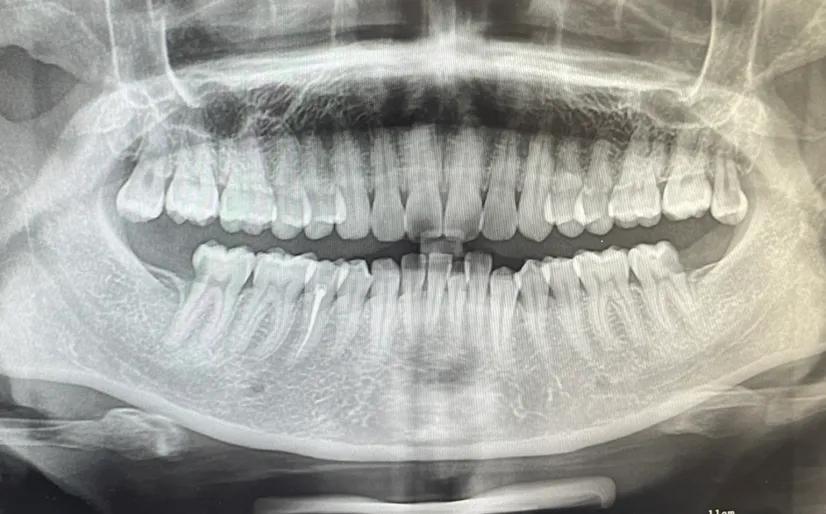

拓展知識(shí):種植牙中間一般要拔多少顆

這個(gè)要根據(jù)患者的實(shí)際情況,不同的患者能承受的不同 。建議到正規(guī)口腔科醫(yī)院【北京三級(jí)口腔醫(yī)院】根據(jù)患者的情況在決定。患者可以在恢復(fù)牙齒咀嚼功能的前提下兼顧牙齒美觀,針對(duì)全口牙齒缺失的患者是可以通過全口種植來恢復(fù)牙齒功能與美觀的,種牙點(diǎn)擊申領(lǐng)種牙補(bǔ)貼

傳統(tǒng)種植牙方式需要二次手術(shù)和3-6個(gè)月修復(fù)期,這對(duì)于怕麻煩追求率的市民或許不太合適,可選擇“即拔、即種、即用”的用種植方案,該技術(shù)是英國愛丁堡大學(xué)贊安南博士帶領(lǐng)實(shí)施的,根據(jù)患者牙槽骨密度、高度、寬度,自動(dòng)避開血管和神經(jīng),以1微米的精度種植牙根,做到即拔即種,一次完成手術(shù)。

一般連續(xù)牙齒缺失的情況是可以進(jìn)行一次種植牙修復(fù)的,并且不需要種植多顆種植體,一般需要連續(xù)缺失5顆或者4顆牙,只需要2到3個(gè)種植體就足夠,在費(fèi)用上也省了不少錢,如果有需求一定要選擇正規(guī)專業(yè)點(diǎn)的口腔機(jī)構(gòu)進(jìn)行缺失牙種植調(diào)節(jié)。

一次可以種植2到3顆,但拔牙一次只能拔一顆,等徹底消炎好了才能拔第二顆。

看什么情況才能做決定,正常能做3顆牙左右,特殊情況滿口牙一起種。